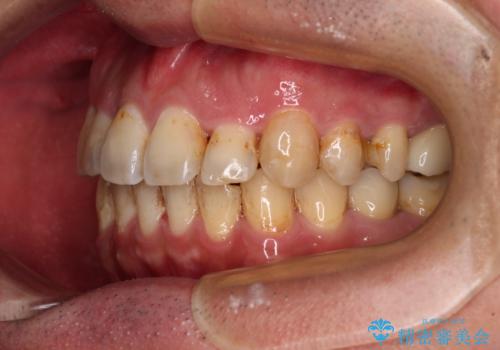

上顎前歯が舌側に転位しており、なるべく早く楽に矯正したいとのことで、ワイヤー矯正を行うこととしました。

矯正治療により歯磨きがしやすくなったので、虫歯予防のセルフケアが行いやすい環境となりました。